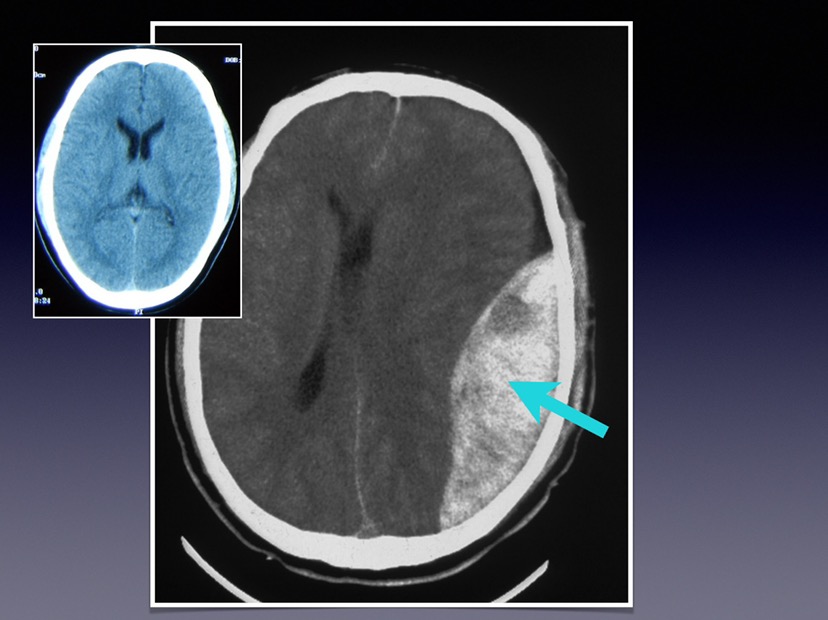

亚急性硬膜外血肿 急性硬膜外血肿 慢性硬膜下血肿

硬脑膜外血肿

硬脑膜外血肿与硬脑膜下血肿鉴别

硬膜外血肿与硬膜下血肿的鉴别pptppt